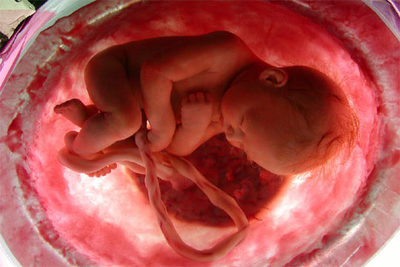

National Geographic Channel ha presentado hoy en Madrid En el vientre materno, un documental que se introduce por vez primera en el interior de un útero materno para filmar, mediante imágenes ultrasónicas, los nueve meses de gestación de un feto humano. Se trata de la primera vez que se ofrece el desarrollo de un embarazo desde dentro y con una buena calidad de imagen. Para emitir la cinta, de dos horas de metraje, el canal ha elegido el simbólico Día de la Madre.

Las imágenes son tan bellas y reales que parece que han logrado meter una cámara en el útero. Pero su realización ha sido posible gracias al empleo de las últimas tecnologías de imágenes ultrasónicas en tres y cuatro dimensiones (3D y 4D), que ofrecen una fotografía nítida y secuencias en movimiento a tiempo real. A estos fotogramas se unen recreaciones hechas por ordenador y además, han filmado, esta vez sí con una minicámara dentro del abdomen de la madre, una operación de un embarazo complicado.

En el vientre materno inicia su viaje la centro de la vida en el mismo momento de la concepción. Por medio de imágenes generadas por ordenador, se acompaña el recorrido del blastocito (embrión de pequeño tamaño), desde la trompa de Falopio hasta el útero, donde se instala y comienza a tejer las primeras células nerviosas. El documental regresa al interior del seno materno tan sólo unas semanas más tarde para mostrar los cambios que se han producido y, así, se puede observar el primer desarrollo del cerebro y la espina dorsal y se asiste al momento de formación del corazón, una masa muscular que comienza a latir de manera espontánea.